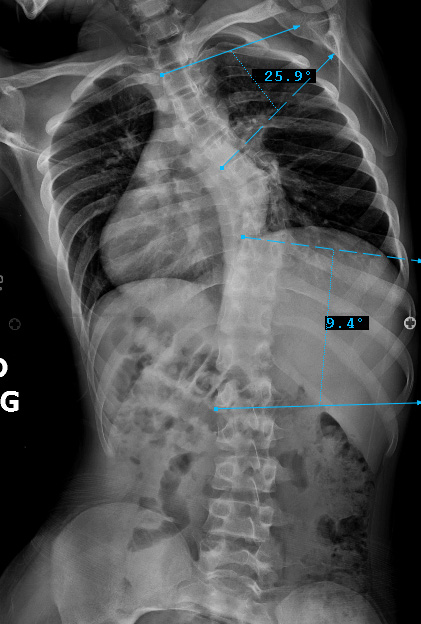

Sagittal Modifier ( + )

T5-T12 in the >40o range

Preop LAT View